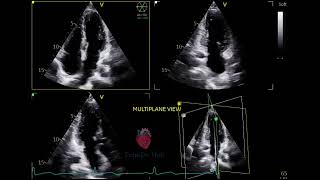

Welcome to EchoDx Hub, your dedicated space for mastering echocardiography through real clinical cases. We specialize in showcasing abnormal echo images and videos, helping you recognize key patterns, understand pathology, and sharpen your diagnostic skills.

To build a high-quality educational archive of diverse echocardiographic abnormalities and cardiovascular diagnostics—for students, sonographers, and healthcare professionals passionate about cardiac imaging.

Authentic case-based echo clips

Diagnostic tips and echo interpretation pearls